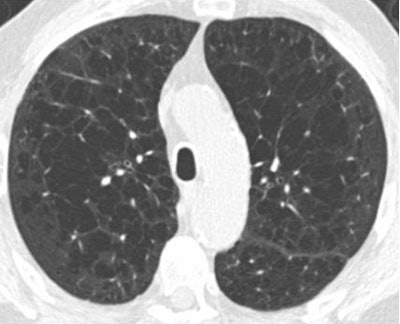

Each reader subclassified each scan as normal or as one of three phenotypes related to COPD: emphysema-predominant, airway-predominant, or mixed-pattern. They looked for centrilobular emphysema (trace, mild, or moderate), paraseptal emphysema, bronchial wall thickening, centrilobular nodularity, and interstitial fibrosis.

"Patients with moderate centrilobular emphysema had a greater distribution of these lucencies, and within this category we included patients who had both confluent areas of emphysema and advanced destructive emphysema with architectural distortion," Chiles explained.

For mild paraseptal emphysema, the focus was on juxtapleural lucencies 1 cm or smaller; for those with moderate disease, the focus was on more substantial juxtapleural lucencies in the mediastinal region.